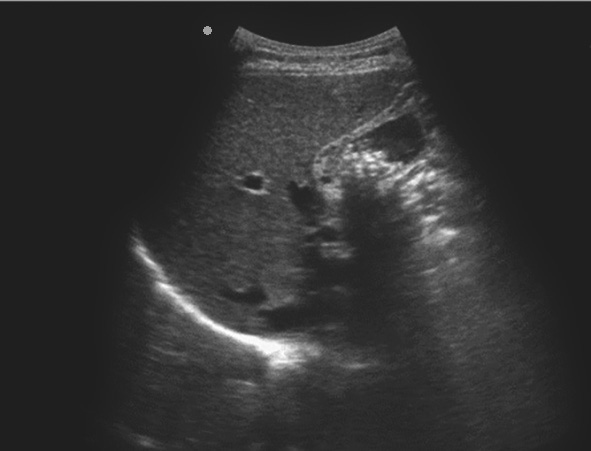

1)充满型胆囊结石:

胆囊内胆汁较少或无胆汁,声像图表现为胆囊前壁呈弧形或半月状的强回声带,后方伴较宽声影,致使胆囊的后壁不显示。另外,此型胆囊结石还有一种特征性的声像图表现:WES征,前方为增厚的低回声胆囊壁,包绕中间的结石强回声带,后方伴声影(图2-6-3A)。

2)胆囊颈部结石:

胆囊颈部结石未嵌顿时,结石在周围胆汁的衬托下易于显示,表现为强回声后方伴有声影;胆囊颈部结石嵌顿时,周围无胆汁的衬托,结石显示不清楚,造成诊断困难(图2-6-3B)。

图2-6-3 非典型胆囊结石灰阶超声图像

A.充满型胆囊结石;B.胆囊颈部结石;C.泥沙样胆囊结石;D.胆囊壁内结石